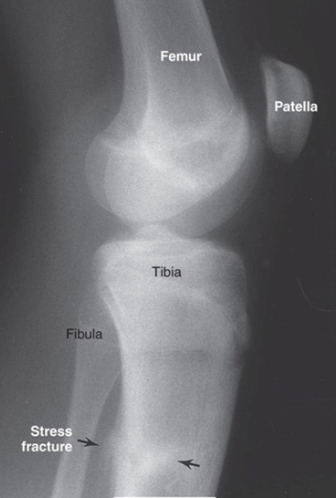

Lateral View of Knee showing Stress Fracture on Tibia as result of Abnormal Stress Overload

Stress Fracture of Distal Fibula

Transverse